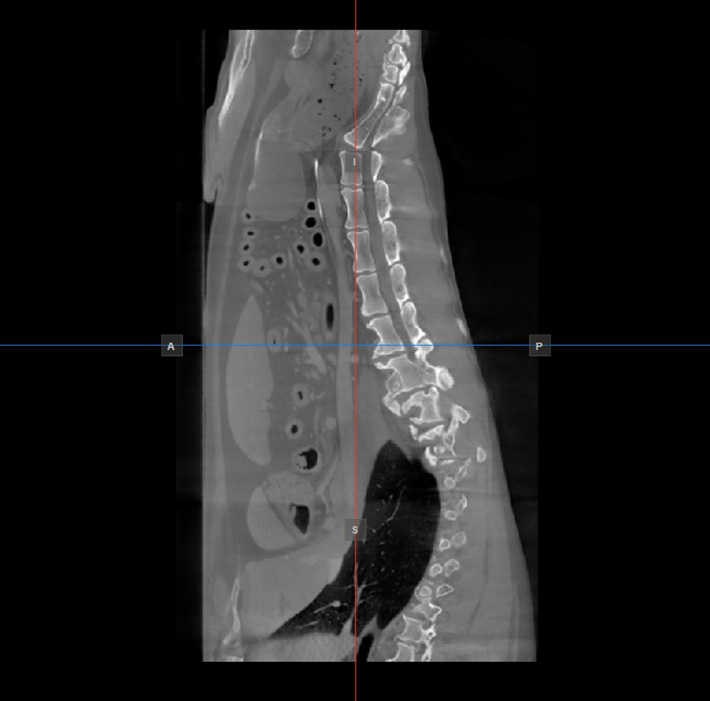

The position and intersection of the other two image planes not represented in the active viewport is indicated by two vertical and horizontal lines called slicers. The endpoints of each slicer are labeled with a letter that corresponds to the appropriate direction/side of the 3D volume, based on the RAS coordinate system.

Only four sides of the available six are indicated on each 2D viewport. The labels and the corresponding side are the following:

Patient Right (R), indicating the right side of the body

Patient Left (L), indicating the left side of the body

Anterior (A), indicating the front side of the body

Posterior (P), indicating the back side of the body

Superior (S), indicating the top side of the body

Inferior (I), indicating the bottom side of the body